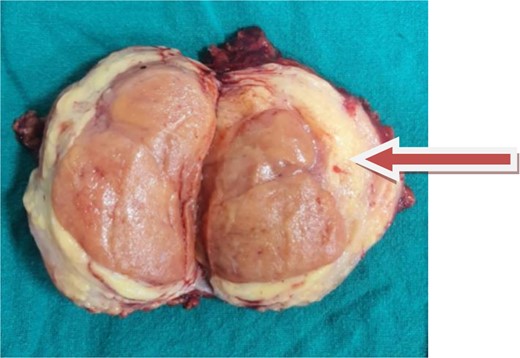

A soft encapsulated mass measuring 12.0 × 8.0 × 1.0 cm with tannish orange cut surfaces was identified in a surgical tissue specimen. The tumor was 2 cm away from the capsule (Fig. 3).